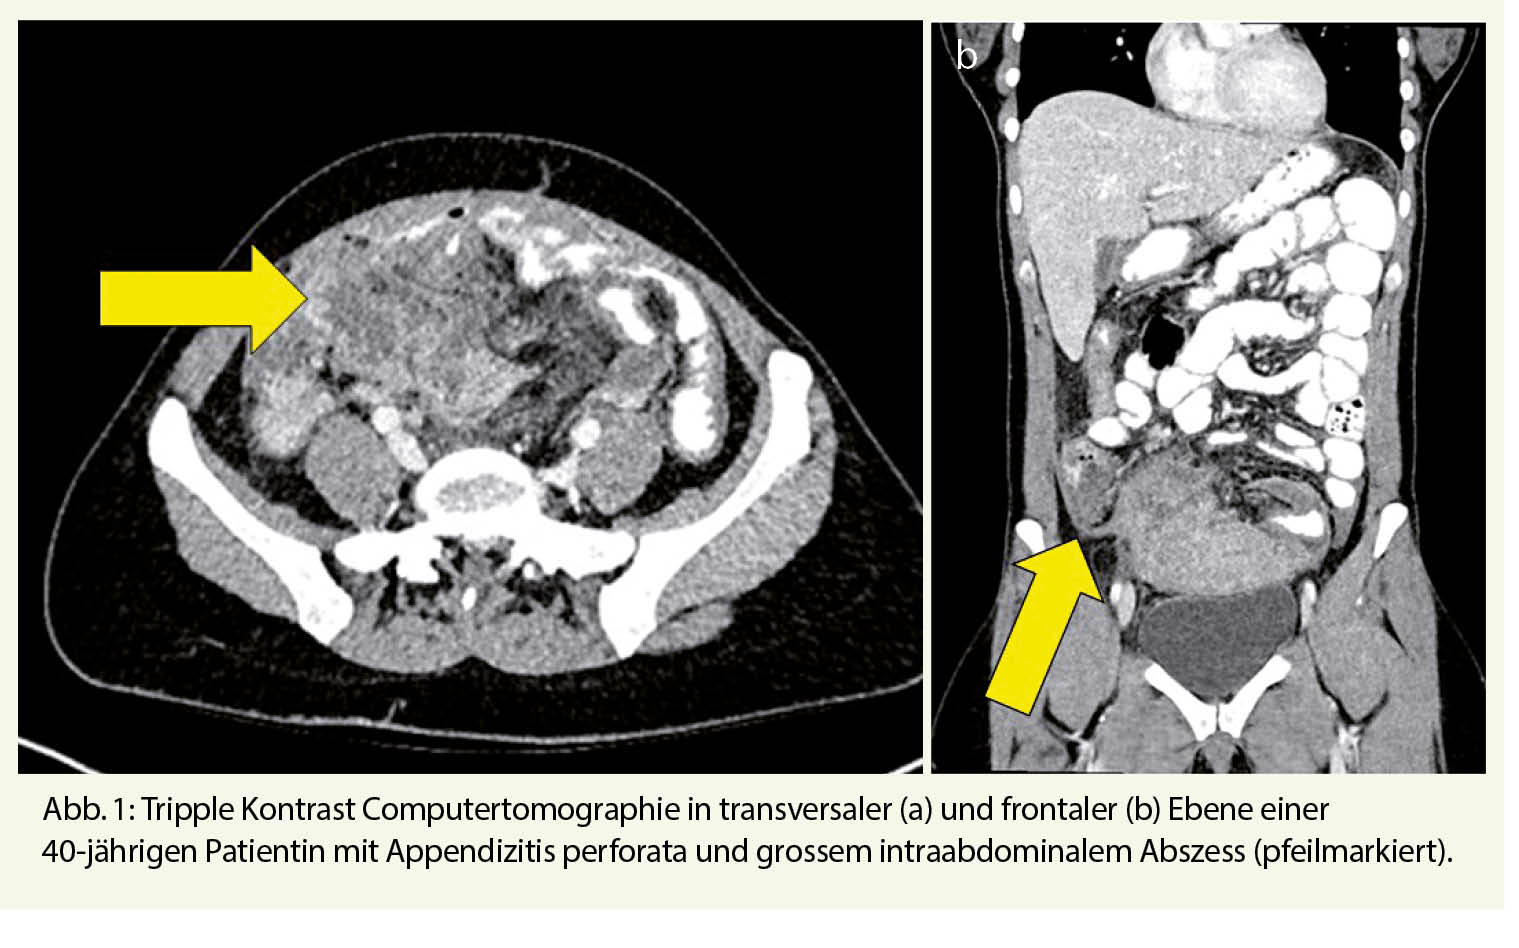

Die Computertomographie ist die Untersuchung der Wahl, dank welcher die Diagnose einer akuten Appendizitis mit einer hohen Spezifität und Sensitivität gestellt werden kann (Abb. 1). Diese Untersuchung ist an vielen Orten zur Standardabklärung bei Erwachsenen geworden. Zur Strahlenreduktion sollte eine «low dose» Computertomographie durchgeführt werden (11). Bei Kindern und jungen Erwachsenen, welchen keine Strahlenbelastung zugemutet werden soll, stellt die Sonographie die erste Wahl dar.

Die präzise Diagnose soll die Unterscheidung zwischen unkomplizierter und komplizierter Appendizitis möglich machen. Dies ist entscheidend, da so der Behandlungsplan auf die Diagnose abgestimmt werden kann.

Von einer unkomplizierten Appendizitis spricht man, wenn kein Appendikolith, keine Perforation und keine freie Flüssigkeit vorhanden sind.

Eine komplizierte Appendizitis entspricht einer Appendizitis perforata mit eitriger oder stuhliger Kontamination der Bauchhöhe bis hin zur Abszessformation im kleinen Becken.